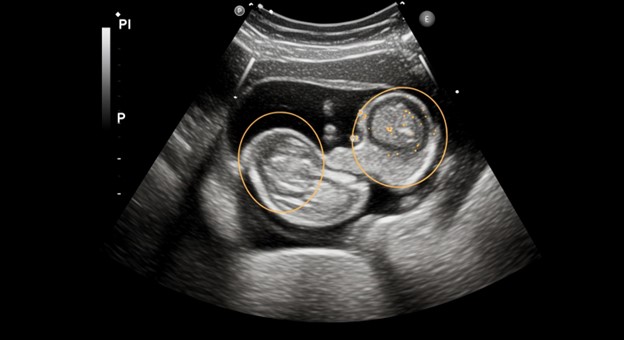

تشوّهات الأجنّة هي اضطرابات تحدث عندما يتطوّر الجنين بشكل غير طبيعي أثناء الحمل، وقد تُؤثّر في جزء من الجسم أو في الجسم كله. وتُعدّ هذه التشوّهات من القضايا الصحيّة المهمّة التي تستدعي اهتمام الأطباء والآباء، إذ قد تنعكس سلبًا على صحّة الجنين ومستقبله

تشوّهات الأجنّة هي اضطرابات تحدث أثناء نمو الجنين، مما يؤدي إلى تطور غير طبيعي في جزء من الجسم أو الجسم كله. تُعتبر هذه التشوّهات من القضايا الصحيّة المهمّة التي تستدعي انتباه الأطباء والأهل، إذ قد تؤثر على صحة الجنين ومستقبله.